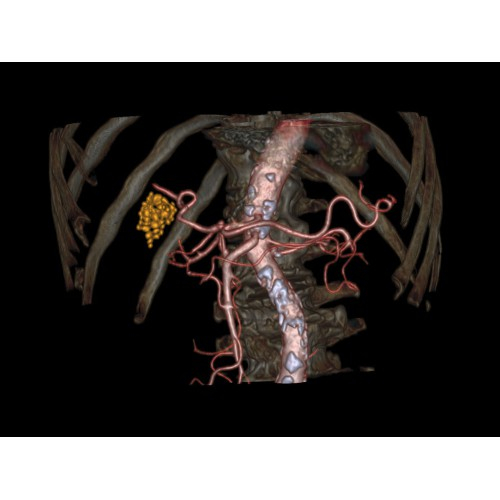

Позволяет проводить комплексные исследования всех анатомических зон, включая нейровизуализацию, ангиографию, исследования органов грудной и брюшной полости. Особенно эффективен для раннего выявления онкологических заболеваний.

Специализированные исследования